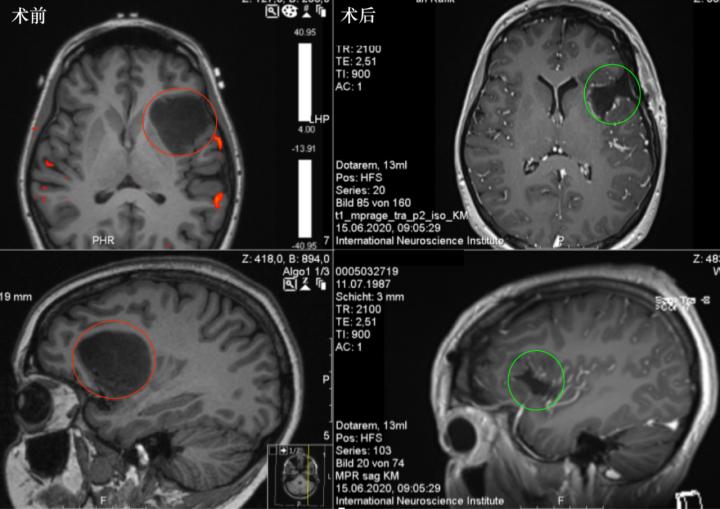

图:术前MR显示岛叶占位,直径约为4cm,紧邻重要脑功能区,包绕左岛叶的大部分,并在背侧延伸至岛叶的后部。术后MR显示肿瘤全切,无脑出血、水肿等正常脑组织损伤。